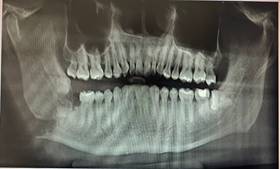

Por último, se realizó un bloqueo maxilofacial semirrígido, con el fin de devolver su funcionalidad y se realizó una radiografía panorámica inmediata. (Figura 3)

Figura 3. Radiografía panorámica poscirugía.

Como parte del tratamiento se prescribieron antibióticos, antinflamatorios y analgésicos, además de cuidados como una termoterapia con frío durante las primeras 72 horas, dieta líquida y se dio indicaciones de cómo mantener una buena higiene. A los 3 meses se realizó el control correspondiente con la toma de una radiografía panorámica donde se evidenció la formación de nuevo tejido óseo.

Como complicación no existió ninguna, después del posoperatorio y de los días de reposo absoluto. La evolución final del tratamiento conservador fue satisfactoria con rehabilitación funcional completa de la arcada afectada, le dio al paciente movilidad masticatoria y ausencia de molestia o dolor.